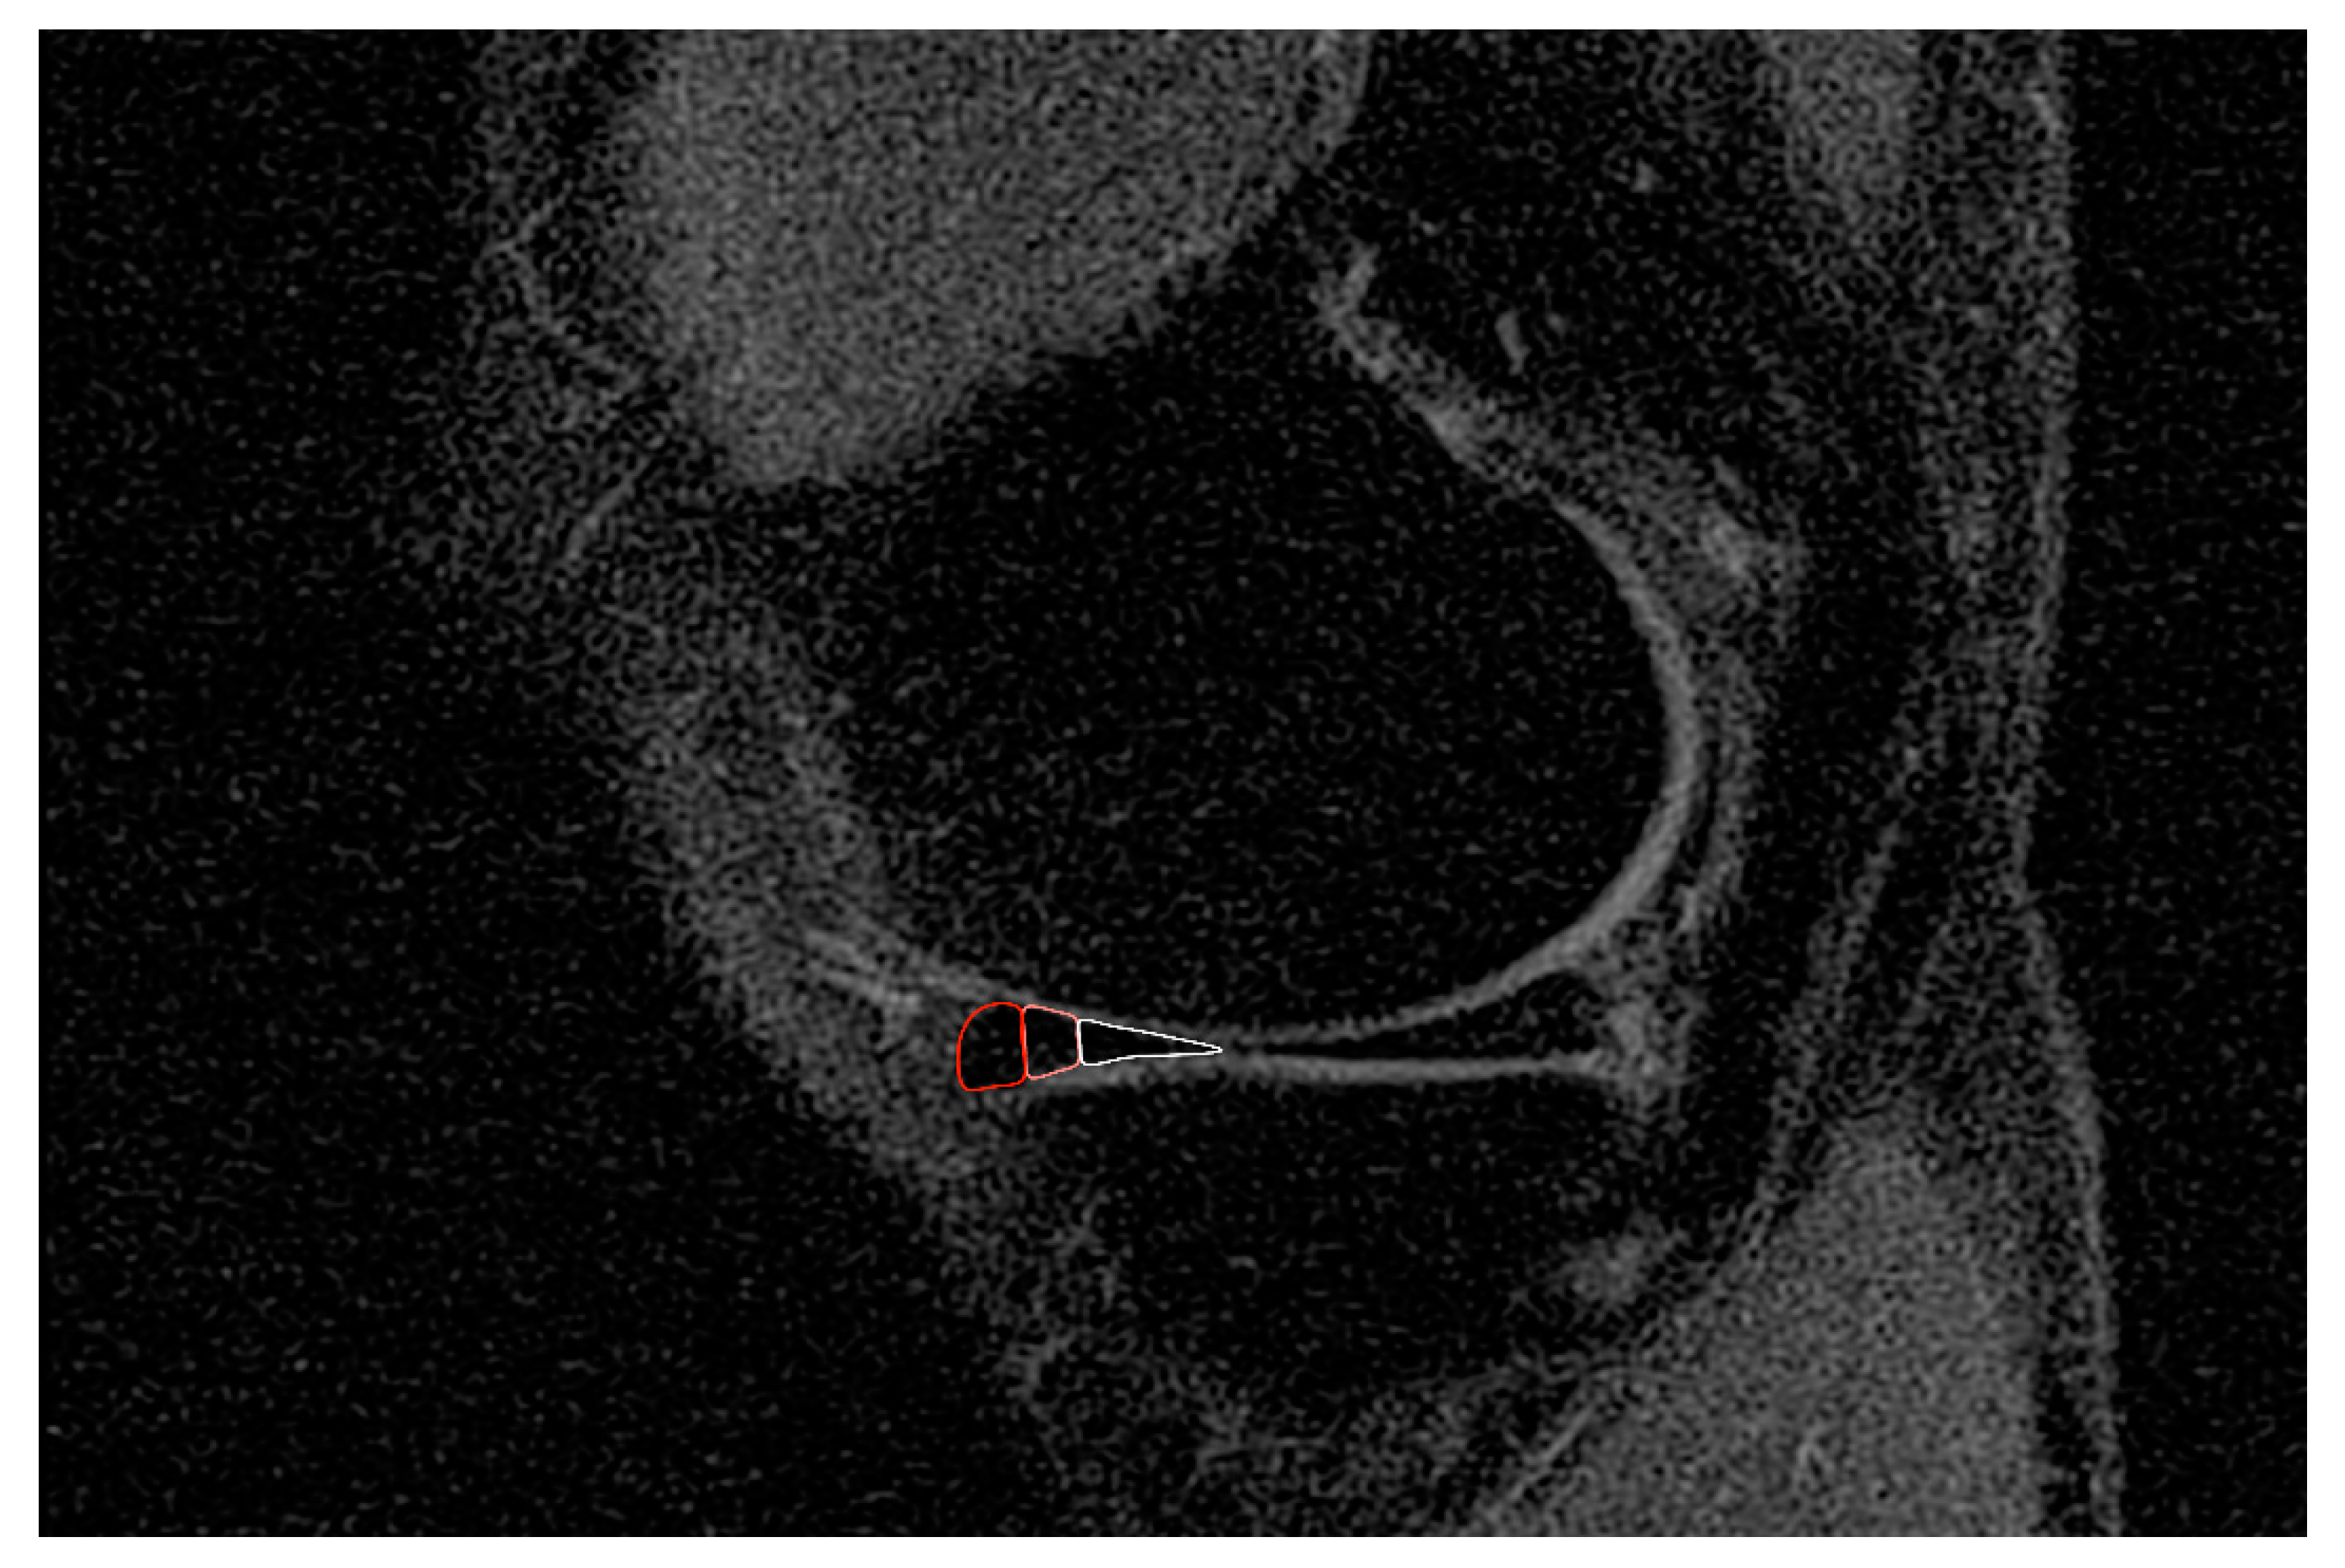

2.5. Evaluation of Healing Effects

3.2. Healing Effects